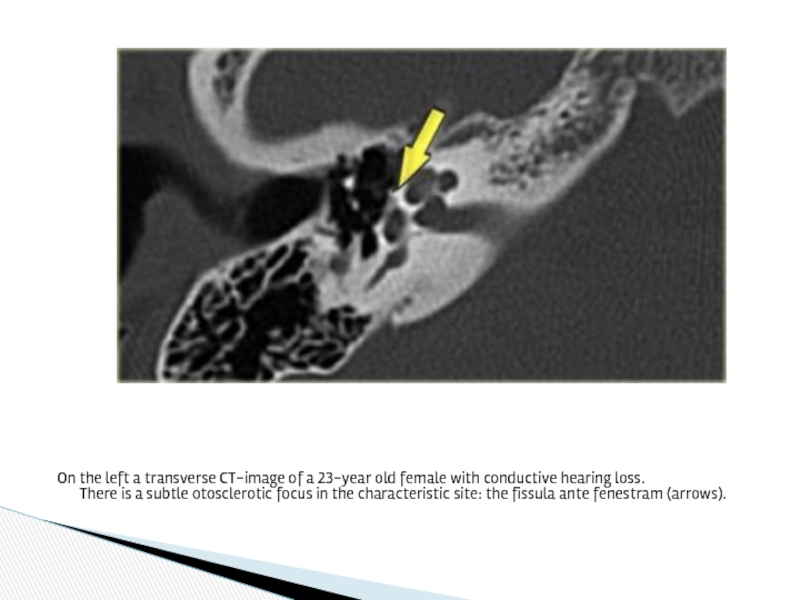

Слайд 26On the left a transverse CT-image of a 23-year old female

with conductive hearing loss. There is a subtle otosclerotic focus in the characteristic site: the fissula ante fenestram (arrows).